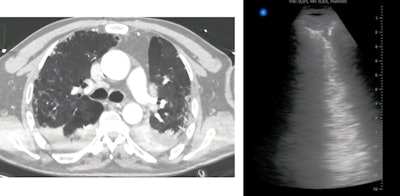

Chen conducted point-of-care ultrasound scans on all patients using a 12-zone protocol. Each zone was assigned a lung ultrasound score (LUS), with higher scores indicating more severe disease.

All patients in the study also underwent chest CT scans, which were read by two radiology trainees under the supervision of a senior radiologist. The radiologists calculated a total CT severity score, and like with a LUS, a higher CT severity score represented more severe lobar involvement.